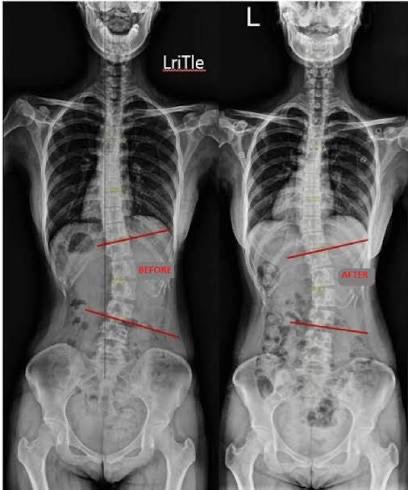

Μέθοδος Schroth για τη Σκολίωση

Η Μέθοδος Schroth είναι μια εξειδικευμένη, παγκοσμίως αναγνωρισμένη φυσικοθεραπευτική προσέγγιση για τη συντηρητική αντιμετώπιση της σκολίωσης. Αναπτύχθηκε στη Γερμανία από την Katarina Schroth στις αρχές του 20ού αιώνα και εξελίχθηκε με βάση τη λειτουργική ανατομία, τη συμμετρία του σώματος και τη στοχευμένη αναπνευστική επανεκπαίδευση ανάλογα με το είδος σκολίωσης του θεραπευόμενου.

Στόχοι της μεθόδου Schroth

• Βελτίωση ποιότητας ζωής

• Βελτίωση συμμετρίας του σώματος

• Μείωση ή σταθεροποίηση της κυρτότητας (Cobb angle)